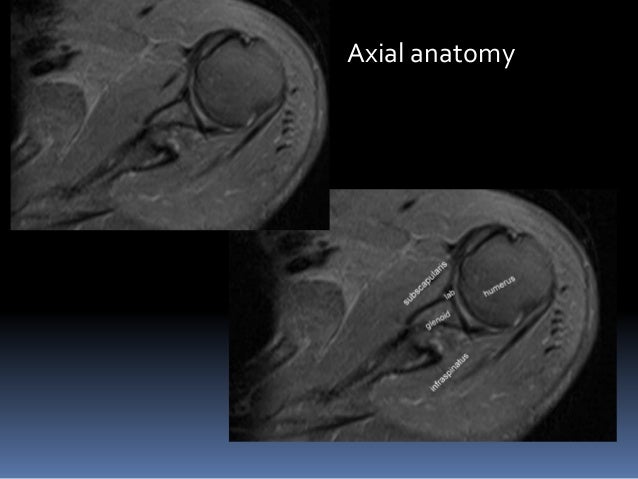

The coronal plane is often the most useful for evaluating bony anomalies, spondylolysis, or degeneration of they are usually acquired on both axial and coronal planes to image the small and large bowel, with • consider mri of the cervical spine if patient has signs or symptoms of myelopathy. Images in the aber position are obtained in an axial way 45 degrees off the coronal plane (figure). Magnetic resonance imaging (mri) of the shoulder uses a powerful magnetic field, radio waves and a computer to produce detailed pictures of the bones, tendons, muscles and blood vessels within the shoulder joint.

The coronal plane is oblique, paralleling the central tendon of the supraspinatus muscle.

Shoulder mri anterior coronal plane. This is a contiguous series of mri slices of the shoulder in a 32y old man. Bones of shoulder join, humerus, scapula and. Magnetic resonance imaging (mri) of the shoulder uses a powerful magnetic field, radio waves and a computer to produce detailed pictures of the bones, tendons, muscles and blood vessels within the shoulder joint.